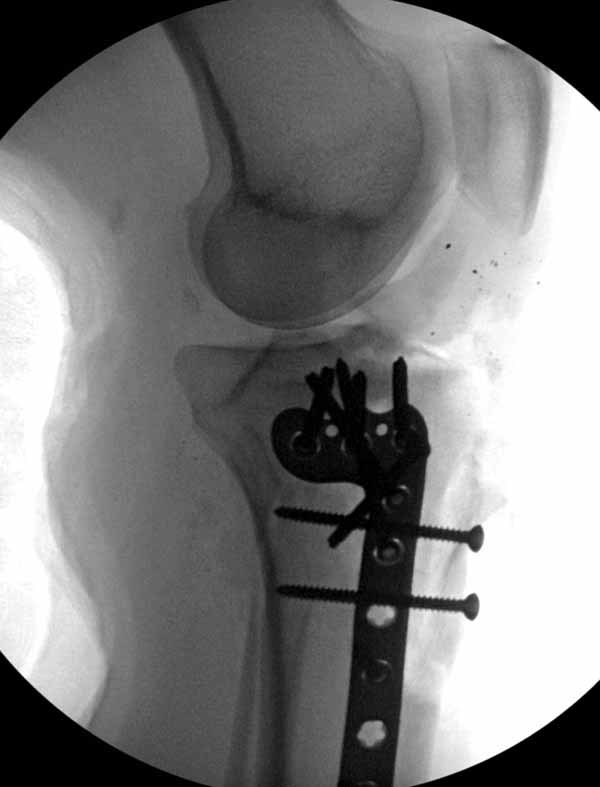

Вложение не в текстовом формате было извлечено…

Имя     : 18 GSW I на D.jpg

Тип     : image/jpg

Размер  : 44777 байтов

Описание: отсутствует

Url     : http://weborto.net:8080/pipermail/ortho/attachments/20110617/500d7d65/attachment-0008.jpg